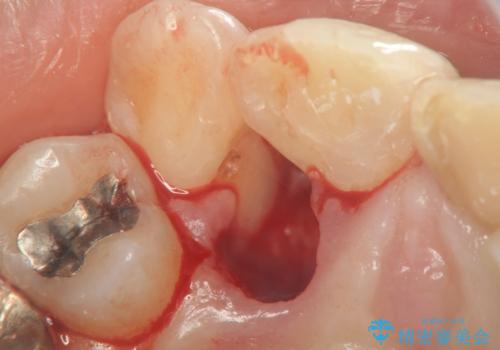

X線写真より不十分な根管治療、根尖病変、前歯の変色が認められます。

歯根の近接のみられる右上側切歯を抜去し、根管治療を伴うセラミック治療を計画します。

叢生が著しく、歯根の近接が見られる場合歯磨きができず歯石がたまりやすく骨吸収の原因となることが多いです。

このような場合矯正や転位歯の抜去が治療方法として挙げられます。